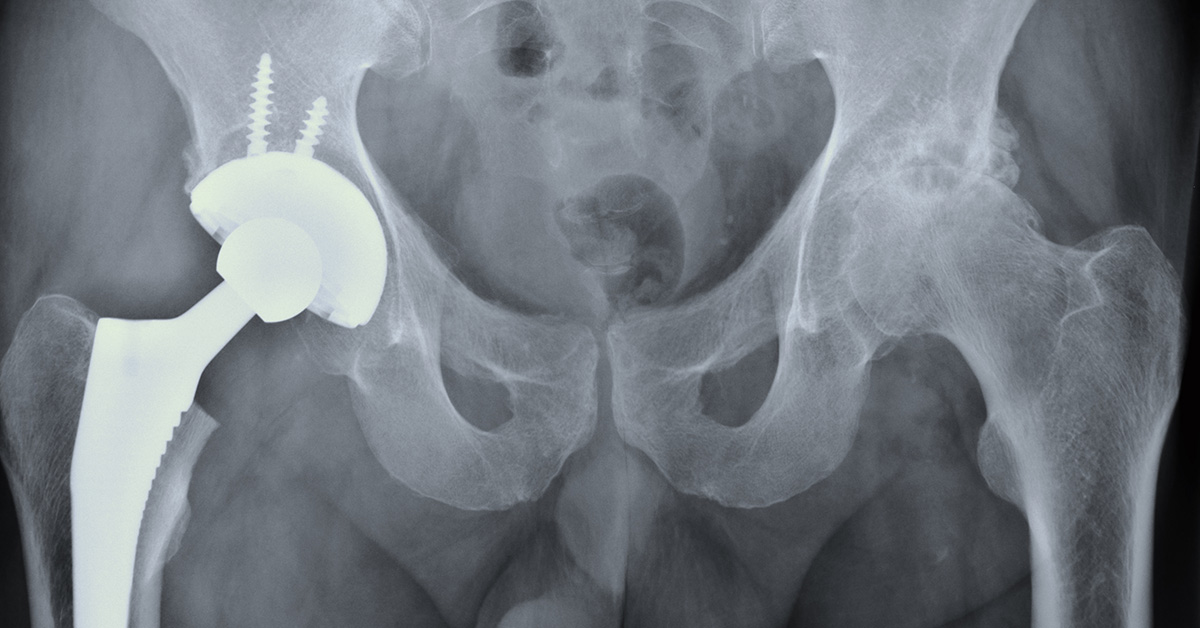

1 Metal on polyethylene total hip replacement. Download Scientific

1 Metal on polyethylene total hip replacement. Download Scientific from www.researchgate.net